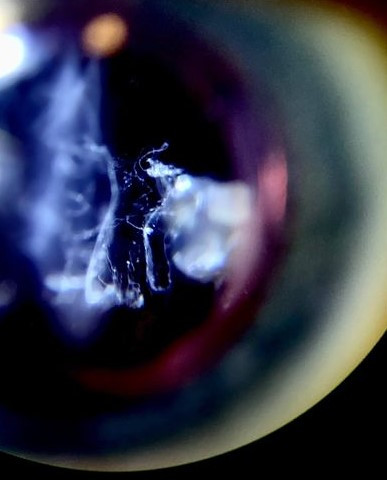

비문증의 가장 대표적인 증상은 눈앞에 떠다니는 작은 점이나 선, 혹은 구름 모양의 물체가 보이는 현상입니다. 이러한 현상은 주로 밝은 배경에서 더욱 잘 보이며, 눈을 움직일 때 함께 움직이는 경향이 있습니다.

비문증은 눈 안의 젤 상태의 유리체가 수년에 걸쳐 액체로 변하면서 발생합니다. 이 변화로 인해 유리체 내부의 작은 덩어리나 섬유가 생길 수 있으며, 이러한 물체가 눈앞에 떠다니는 것처럼 보이게 만듭니다.